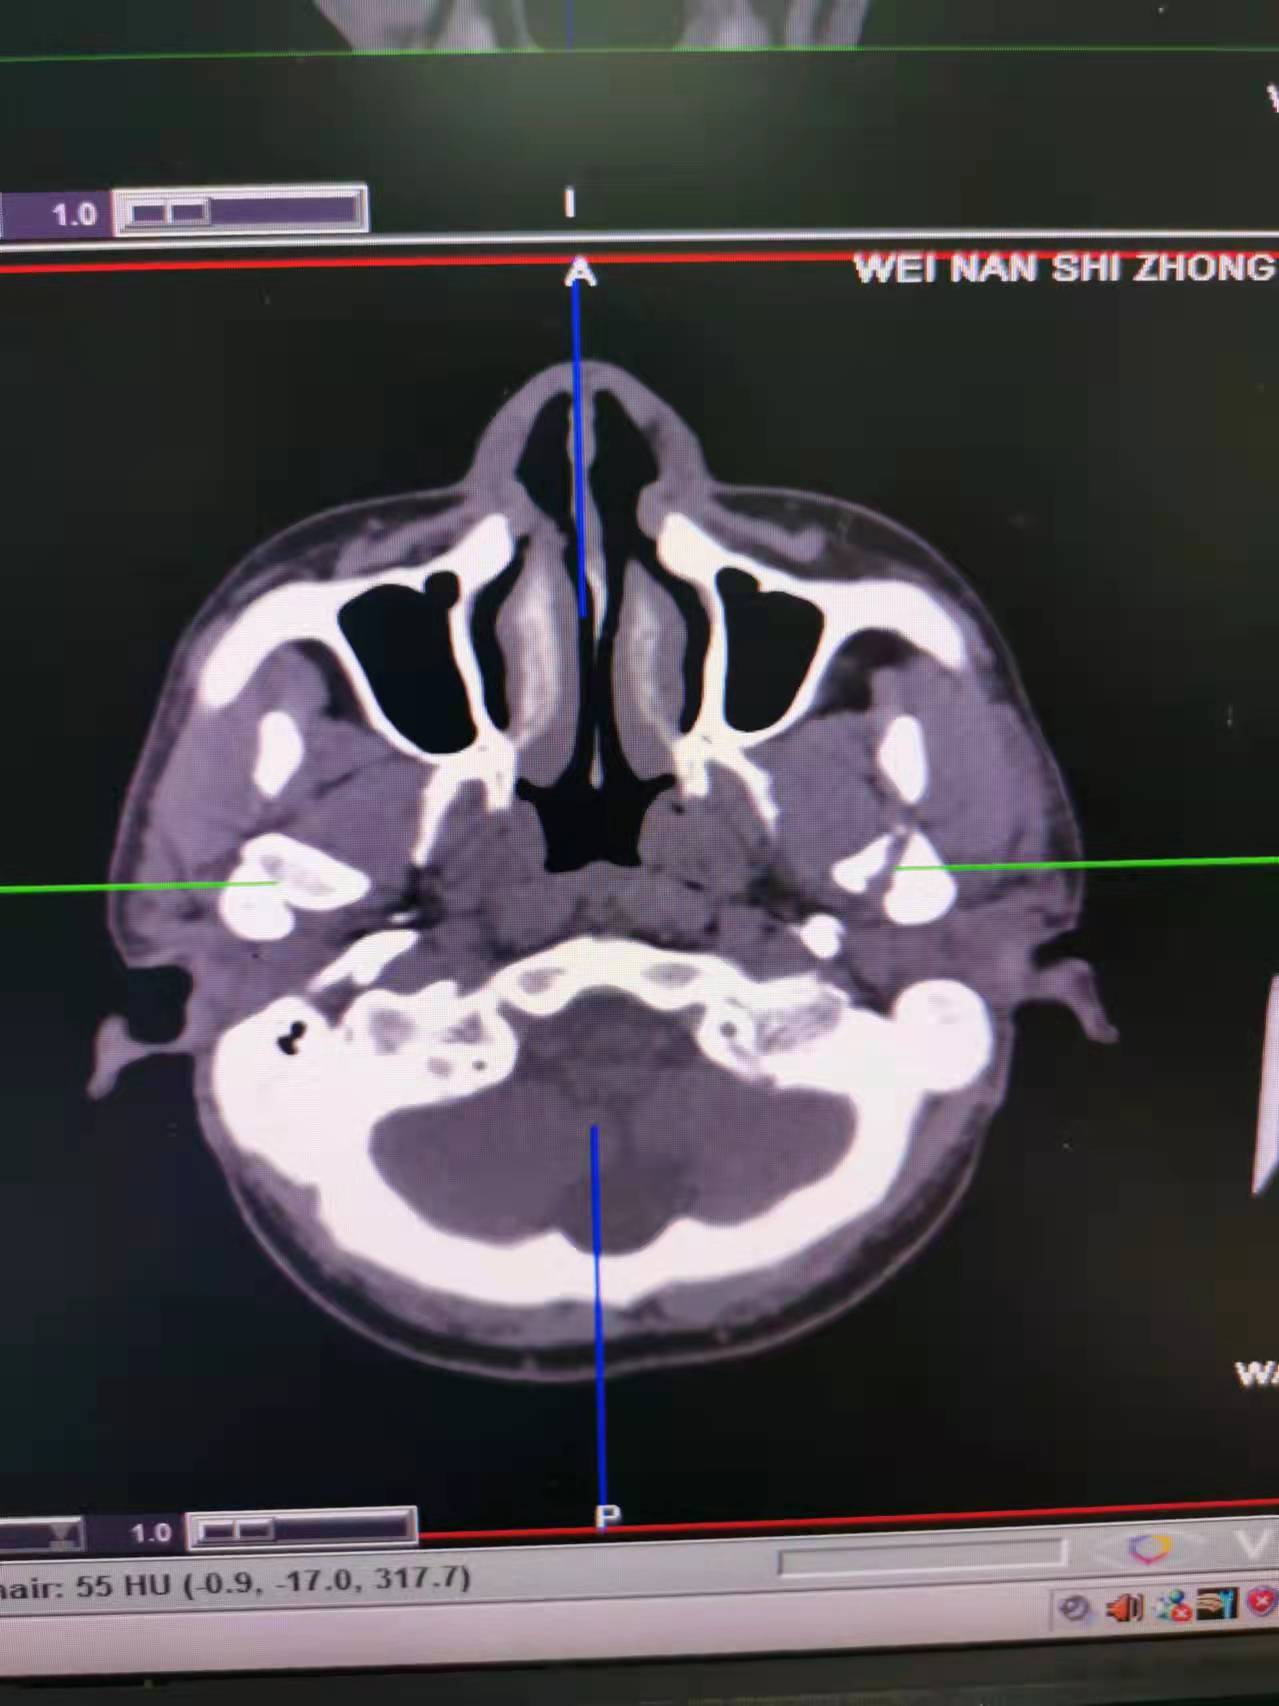

据了解,53岁的患者刘先生在1月25日当天走路不慎摔倒致下颌损伤,造成颏部软组织裂伤和张口困难,前往当地卫生院进行颏部裂伤清创缝合术。术后辗转到乐鱼手机站入口口腔科门诊就诊,并进行颌面部CT检查提示为下颌颏部正中和双侧髁状突骨折,双侧下颌升支高度不一致,右侧较左侧变短1cm,张口重度困难,咬合关系错乱。刘先生因考虑在春节过后再入院治疗,于2月8日再次前来口腔科以“下颌骨骨折”收治人院。

口腔科主治医师蔺非非为患者入院后进行完善术前常规检查和颌间牵引恢复咬合关系。科主任李瑞春结合患者实际病情和检查结果认为,患者的髁突骨折在下颌骨骨折中所占比例较高,约为17.0%-36.3%。髁突骨折时,耳前区有明显的疼痛,局部肿胀、压痛。通过手指深入外耳道或在髁突部触诊,如张口时髁突运动消失,可能有骨折段移位。双侧低位骨折时,2个髁突均被翼外肌拉向前内方,双侧下颌支被拉向上方,可出现后牙早接触,前牙开秴。髁状突骨折易引起下颌后缩,张口困难,咬合关系错乱,关节强直等并发症。考虑患者系陈旧性骨折应尽早实施手术,避免骨折导致的张口困难、关节强直等并发症。因患者已经错过最佳治疗时期,决定尽快为患者进行手术治疗。

科主任李瑞春和主治医师蔺非非经过缜密的术前讨论和充分评估,手术在全身麻醉下进行,术中克服术野狭小操作不便困难,将下颌骨骨折完好对位,顺利地完成了"双侧髁状突和下颌颏部正中骨折切开复位内固定术"。术后检查患者面部对称,双侧下颌升支高度一致,咬合关系已恢复。